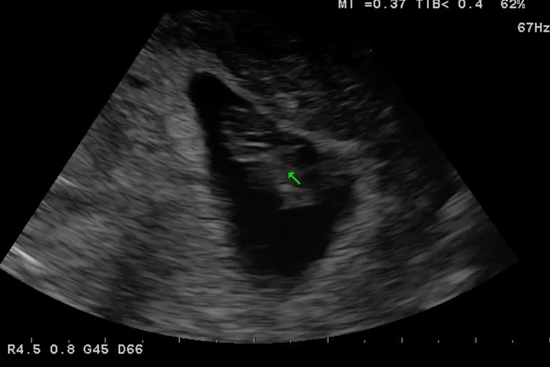

Today, I’m 8 weeks and my 8-week scan was perfect, perfect length, 180 bpm heart rate, and my ovaries and uterus are perfect.